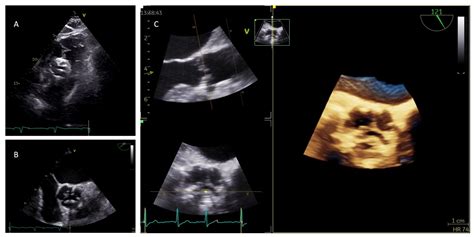

A transesophageal echocardiogram is a more specialized, semi-invasive imaging technique. In this procedure, a thin, flexible tube (endoscope) with an ultrasound probe at the tip is passed down the patient's throat and into the esophagus. Because the esophagus sits directly behind the heart, this approach provides a much clearer, high-resolution view of cardiac structures that may be obscured by the ribs or lungs during a standard TTE.

TEE is typically reserved for scenarios where TTE images are inconclusive or when specific parts of the heart need to be visualized with high precision. Common indications for TEE include:

• Detailed evaluation of prosthetic heart valves.

• Assessing for infective endocarditis (infection of the heart valves).

• Evaluating complex structural heart issues or aortic conditions.